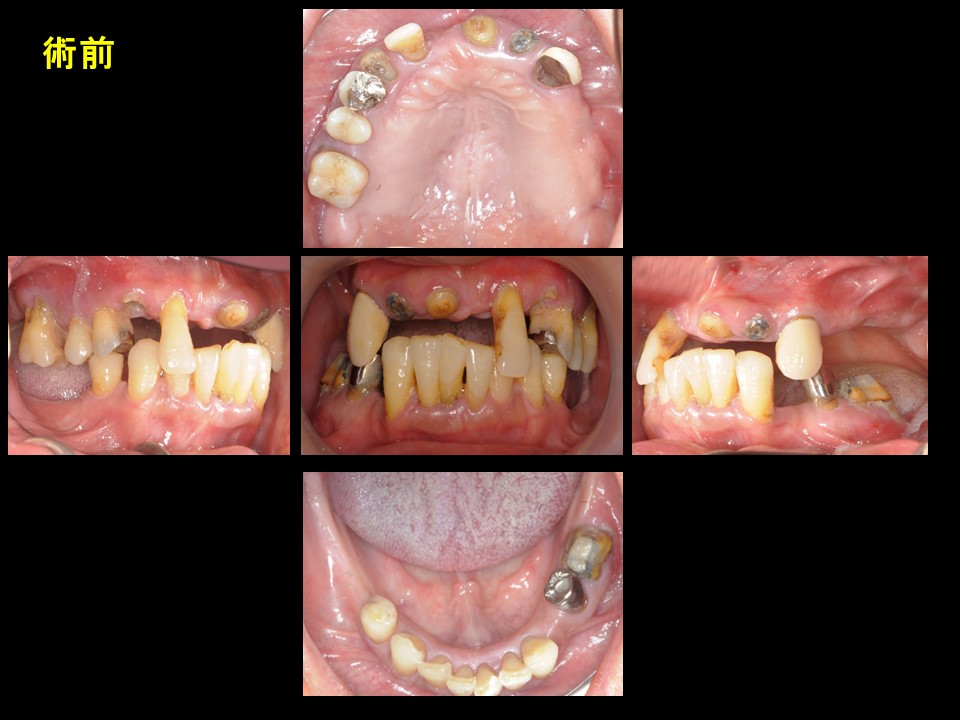

症例1